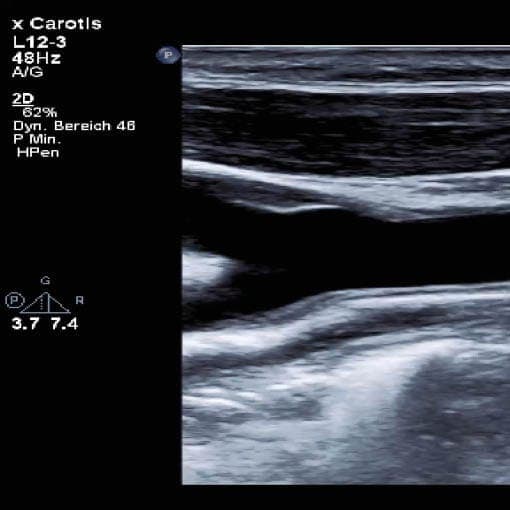

Bild: Duplex-Sonographie der Halsgefäße. Die Gefäßwand (links) und der Blutfluss (rechts) können zeitgleich dargestellt und untersucht werden

Die Duplex-Sonografie erlaubt die zeitgleiche Untersuchung von Gefäßwand und Blutfluss mittels Farb-Doppler. Farbkodiert kann hier die Geschwindigkeit des Blutes dargestellt werden. Mit dieser Methode können Engstellen, die zu einer Reduktion des Blutflusses führen, sicher detektiert werden. Mittels der Spectral-Doppler Technologie kann die Geschwindigkeit in der Engstelle und vor der Engstelle genau vermessen werden, so kann die prozentuale Verengung bestimmt werden.